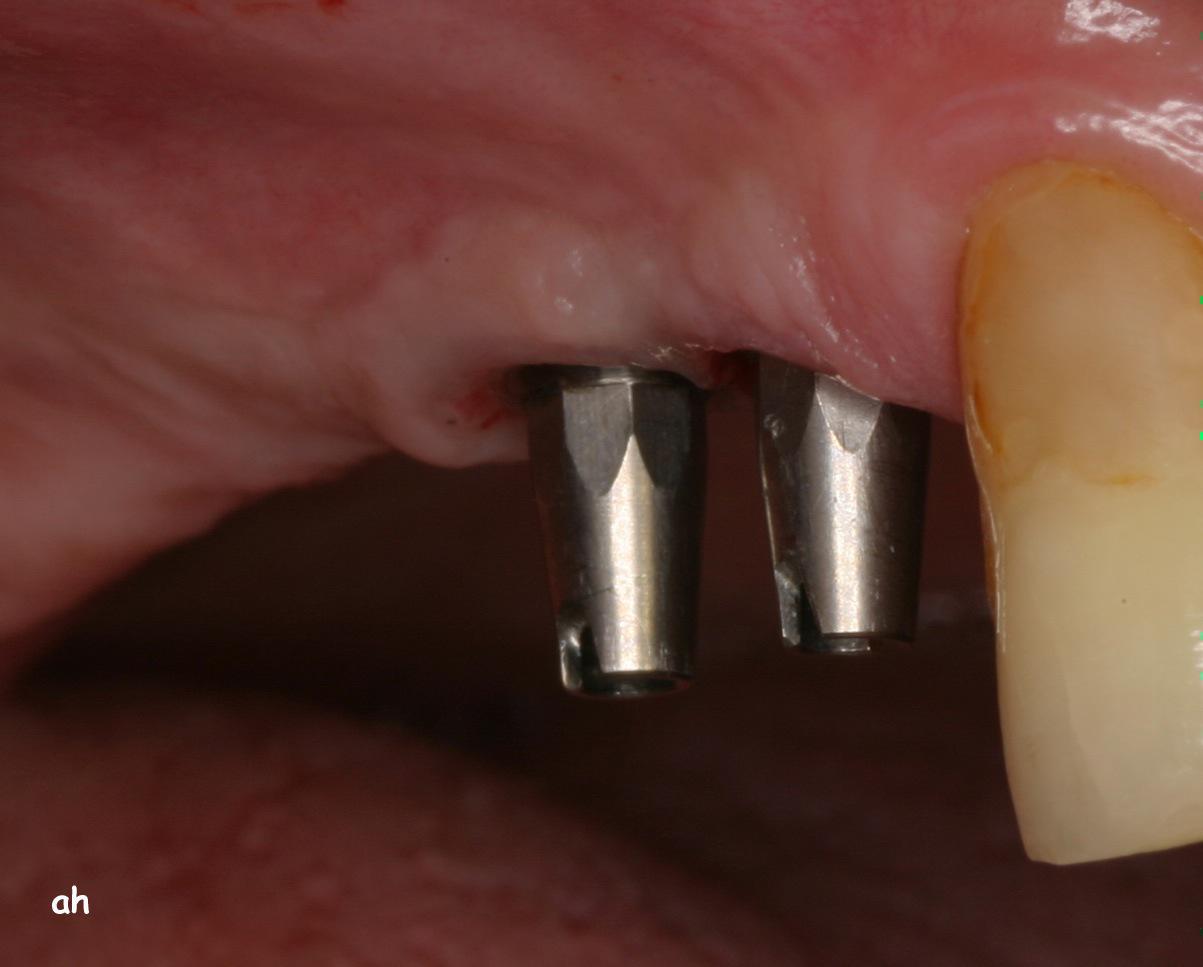

Exemple 9: Un cas complexe, 3 implants on été mis au niveau de la mandibule.

Exemple 9: Une barre est vissée sur ces 3 implants.

Exemple 9: Puis un appareil amovible est fixé sur cette barre.